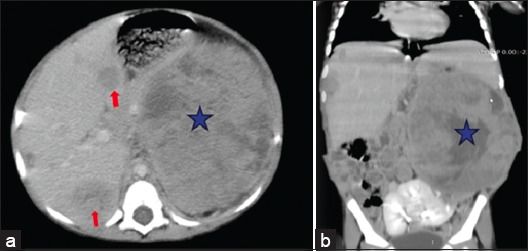

Case description: We are reporting a case report of Wilms tumor in a 3-year-old girl who presented with a huge left flank mass with cross-fused renal ectopia. After the initial workup and triphasic computed tomography scan of the chest, abdomen, and pelvis for confirmation of diagnosis and metastasis, the patient underwent image-guided tissue biopsy, followed by neoadjuvant chemotherapy, left radical nephrectomy with separation of fused right ectopic renal moiety, and adjuvant chemoradiation.